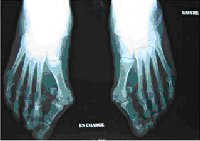

Architecture d’un avant pied normal

La phalange du gros orteil et le premier métatarsien sont pratiquement dans le même alignement.

- Hallux valgus

Le but des techniques chirurgicales traitant l’hallux valgus est de rétablir l’équilibre de l’avant-pied en ramenant le premier métatarsien vers le second et en réalignant le métatarsien et la phalange du gros orteil. Ces traitements ne se contentent pas de « raboter » la bosse (exostose) mais s’attaquent à la cause de la déformation en réduisant l’angle entre le métatarsien et la phalange.